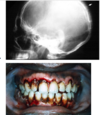

Which systemic disease manifests like this?

Crohn Disease

- Patients can also get angular cheilitis

- Above the Linear ulceration, can see a flap like structure which is the hyperplastic margin